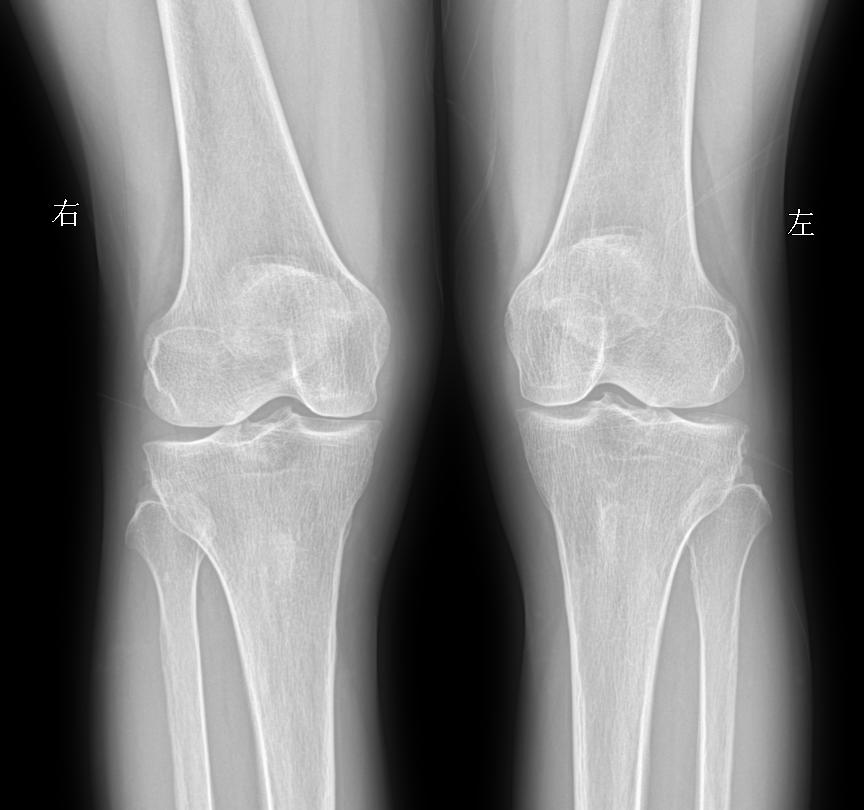

行走膝盖 脚底疼痛就诊 女69岁 考虑什么问题?